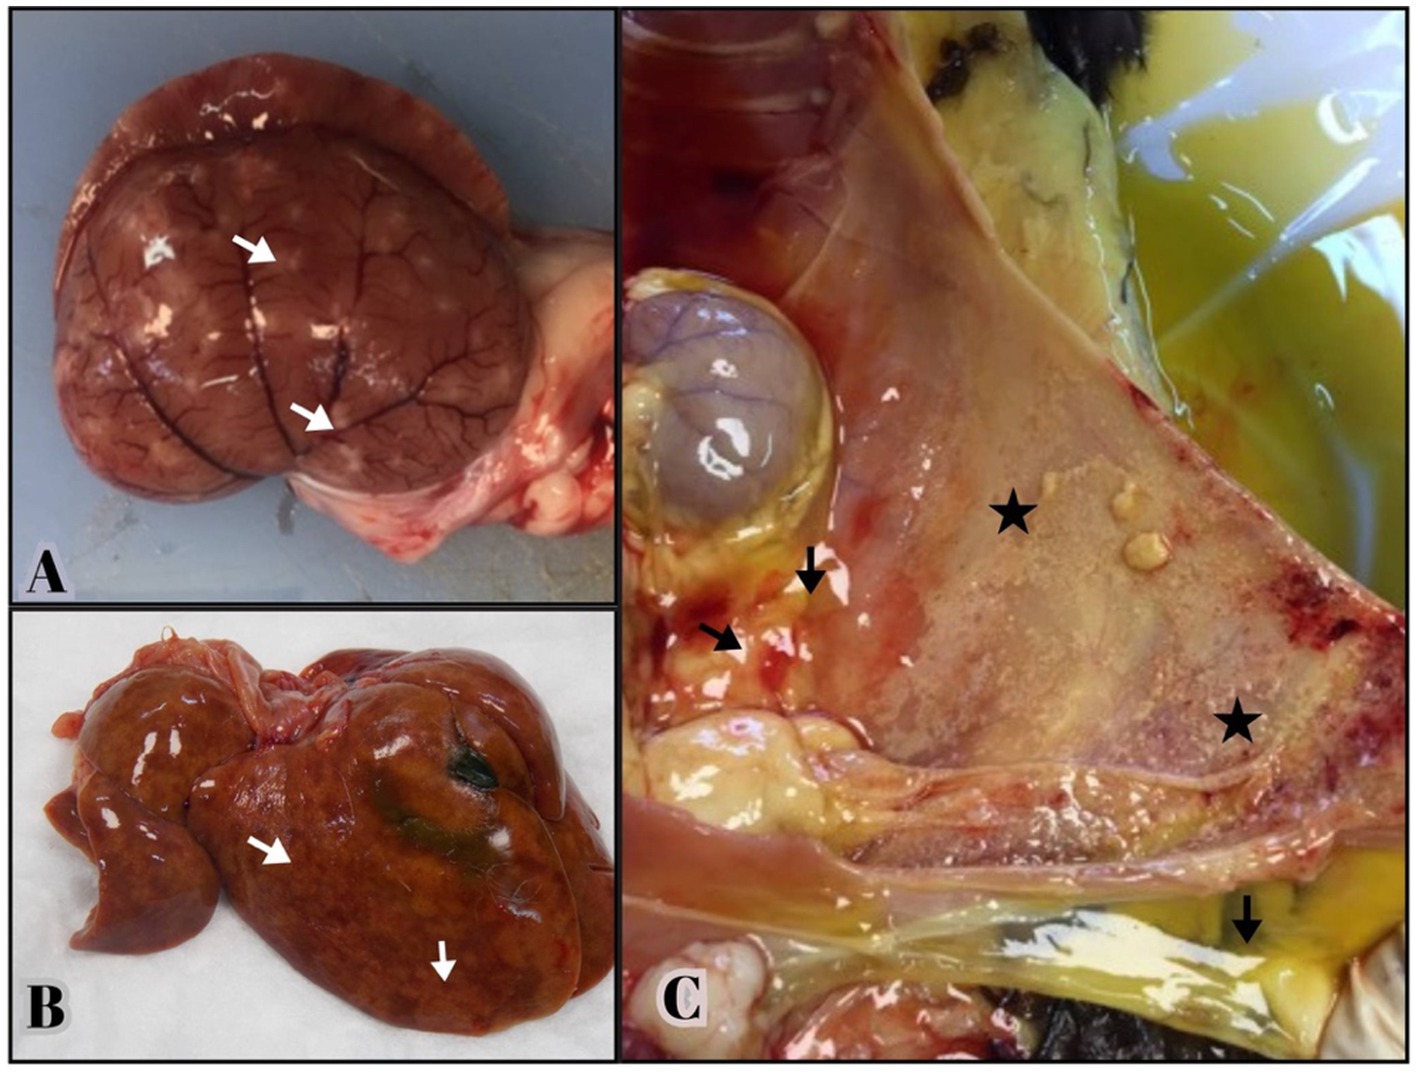

Necropsy revealed fibrinous, yellowish effusion in the body cavities of 19 out of the 43 deceased cats (44.1%). Abdominal effusion was present in 16 cats (37.2%), while thoracic effusion was observed in 9 cats (20.9%), with 6 cats (13.9%) exhibiting both. Abdominal and thoracic effusions (13.9%). Fibrin deposition was particularly prominent in the liver and peritoneum of 16 cats, often accompanied by severe adhesions between abdominal organs. Multifocal granulomatous lesions were detected in 17 cats, primarily the liver and kidneys, followed by the lungs (37.2%) (Figures 1A,B).

Three labeled photographs illustrating gross lesions in cats with feline infectious peritonitis (FIP). (A, B) Multifocal granulomas (arrows) are visible on the kidney capsule and liver surface, extending into the underlying parenchyma. (C) Yellowish, viscous abdominal fluid (arrows) is present in the peritoneal cavity. The serosal surface of the abdominal wall shows small yellow-tan nodules and fibrin deposits (stars), consistent with pyogranulomatous inflammation.

Figure 1. Gross lesions from necropsied cats positive for FCoV RNA by qRT-PCR and histologic lesions consistent with FIP. (A,B) Multifocal granulomas (arrows) are evident on the capsular surface of the kidney, extending into the renal parenchyma and on the surface of the liver. (C) Yellowish, viscous fluid is visible in the abdominal cavity (arrows). The serosal surface of the abdominal wall consists of small yellow—tan nodules and fibrin deposition consistent with pyogranulomatous inflammation (stars).